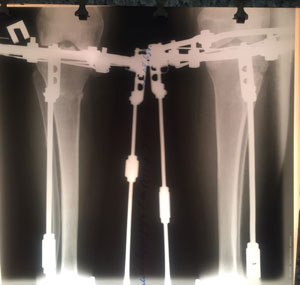

Исходник - 25 лет.

Диагноз: вальгусная деформация голеней (Х - образная)

Дата операции - 16.07.2019г.

IMG_4305-16-07-19-10-13.JPG

IMG_4309-16-07-19-10-13.JPG

IMG_4303-16-07-19-10-13.JPG